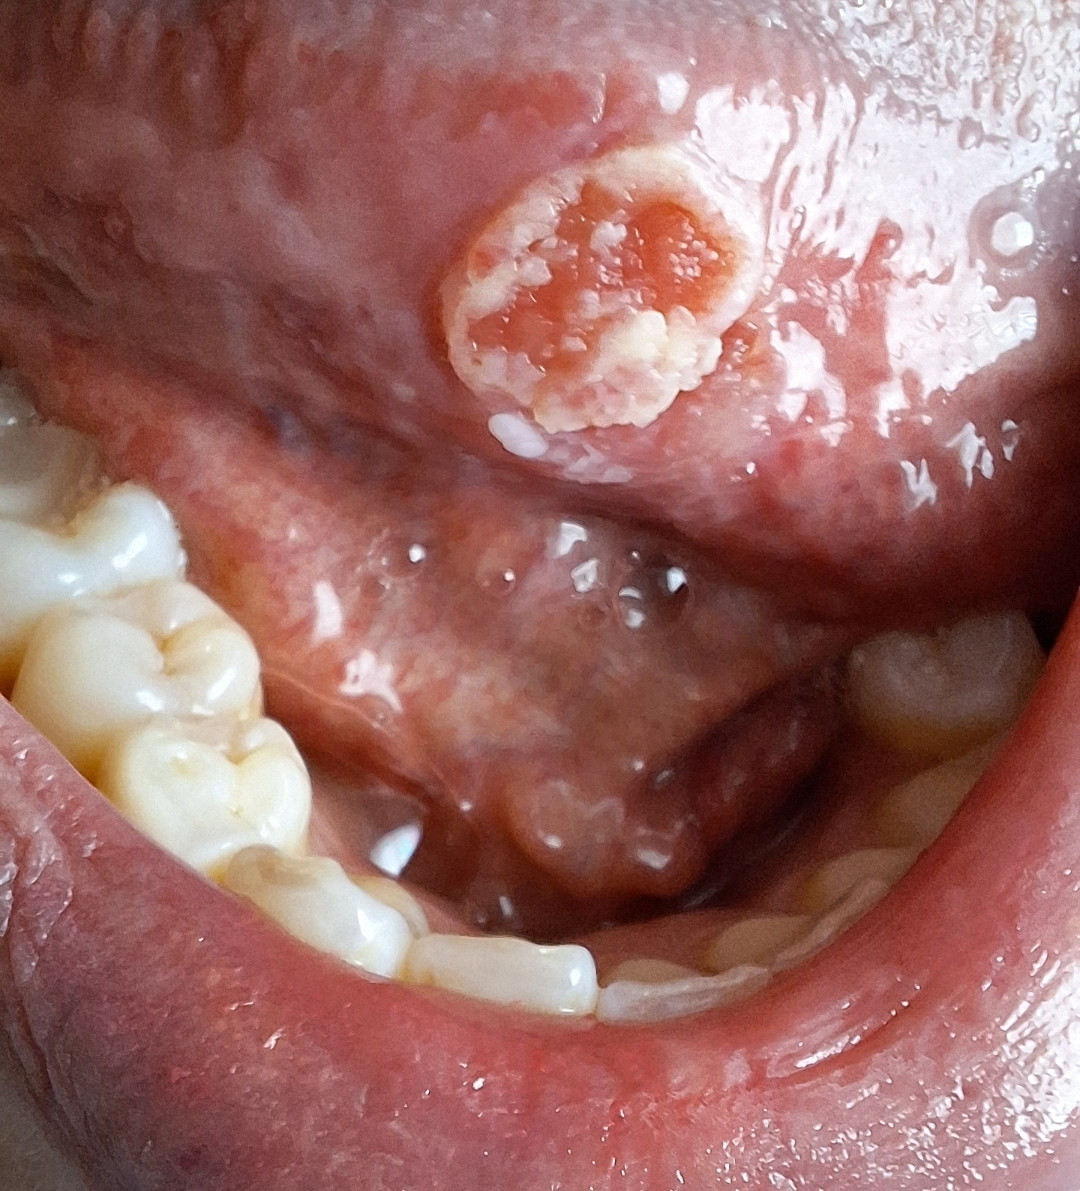

Dinsdag 22 april 2025 mag ik dan eindelijk naar het ziekenhuis. Je bouwt toch een spanning op. Zoekt naar bevestiging maar eigenlijk een geruststelling. Ik heb een afspraak bij een zeer ervaren dermatoloog. Ik krijg een aantal vragen en vervolgens mag ik plaatsnemen op de onderzoeksbank. Tong uitsteken en lamp erop. De dermatoloog kijkt maar weet zo ook niet wat het is. Of hij had al een vermoeden maar durfde het niet uit te spreken tot het tegendeel bewezen is. Dat snap ik dan ook wel weer. Mijn ogen dwalen ondertussen, met mijn mond open, af naar het folder rek. Allemaal bekende termen en instructies van zalven. Ze blijven even hangen op een plaveiselcelcarcinoom. Die had ik ook al gegoogeld, en we hebben overeenkomsten, maar ik parkeer even die gedachten. De dermatoloog stelt een biopt voor. Tong verdoven en een hapje eruit voor onderzoek. " Volgende week vrijdag 2 mei wordt u gebeld met de uitslag".

Wachten duurt best lang en we zijn al even onderweg zonder diagnose. Ik merk dat het plekje groter en gevoelig begint te worden. Tijd voor duidelijkheid. Dinsdagavond zitten wij samen buiten en kan het niet laten om even in te loggen in mij omgeving van het ziekenhuis. Ik weet het, moet je eigenlijk niet doen want je kunt er op dat moment niks mee als het goed of fout is. Het heeft altijd toelichting nodig. Een heleboel moeilijke woorden en termen verder en jawel het woord staat er, plaveiselcelcarcinoom. Kut, zou het dan toch? Er staat bij dat het nog door een tweede laborant bevestigd moet worden. Maar er is wel iets gaande wat niet goed is. Vol ongeloof zitten we samen te huilen omdat we al wel aanvoelde dat het niet pluis was. Maar we hebben nog geen arts gesproken en het onderzoek is nog niet afgerond. Wel pakken we Google erbij voor meer informatie. Plaveiselcelcarcinoom op de tong komt niet vaak voor en als het voorkomt is het vaak bij de 60+, man, roken, alcohol of het HPV virus. Gek, aan geen van alle criteria voldoe ik. Ik probeer het te parkeren maar ga toch een onrustige nacht tegemoet.

Op donderdag 1 mei hebben de kinderen weer een studiedag en ik weer een dag vrij. We hebben boodschappen gedaan en zie plots een gemiste oproep van het ziekenhuis. Shit, ze bellen een dag eerder dan was afgesproken. Foute boel? Ik zet de kinderen voor de TV, loop naar boven en bel terug. Al snel krijg ik een dermatoloog aan de lijn. "Mevrouw u heeft een Plaveiselcelcarcinoom op uw tong en die hoort daar niet te zitten. De KNO-arts wilt u graag vandaag nog zien en beoordelen want we weten niet of we u hier kunnen behandelen want dit komt niet vaak voor". Dan zakt de grond even onder je voeten vandaan. Mijn brein krijgt een error. Ik? Tongkanker? Ik moet 2 uur later al aanwezig zijn. Ik schiet in de regel modus. Mijn man werkt op dat moment anderhalf uur van huis. Snel bellen. Huilend probeer ik de boodschap over te brengen. Hij komt eraan. Die reis voor hem moet ook hels zijn geweest. Ik bel de familie en collega's. Iedereen is geschrokken en leeft met ons mee. Mijn zus komt voor de kinderen, m'n moeder en schoonmoeder zijn onderweg. Collega komt ook een knuffel brengen. Alles is ineen  anders. Bizar. Mijn man is gelukkig op tijd thuis en kunnen we door naar de KNO arts. We praten even over het slechte bericht en de arts wil graag even kijken naar de plek. Hij geeft al vrij snel aan dat ze dit niet in het plaatselijk ziekenhuis kunnen behandelen en wordt direct verwezen naar het UMC Utrecht. Met 15min zitten we weer in de wachtruimte. De assistente neemt ondertussen contact op met de poli van het UMC. Woensdag 7 mei heb ik de afspraak.